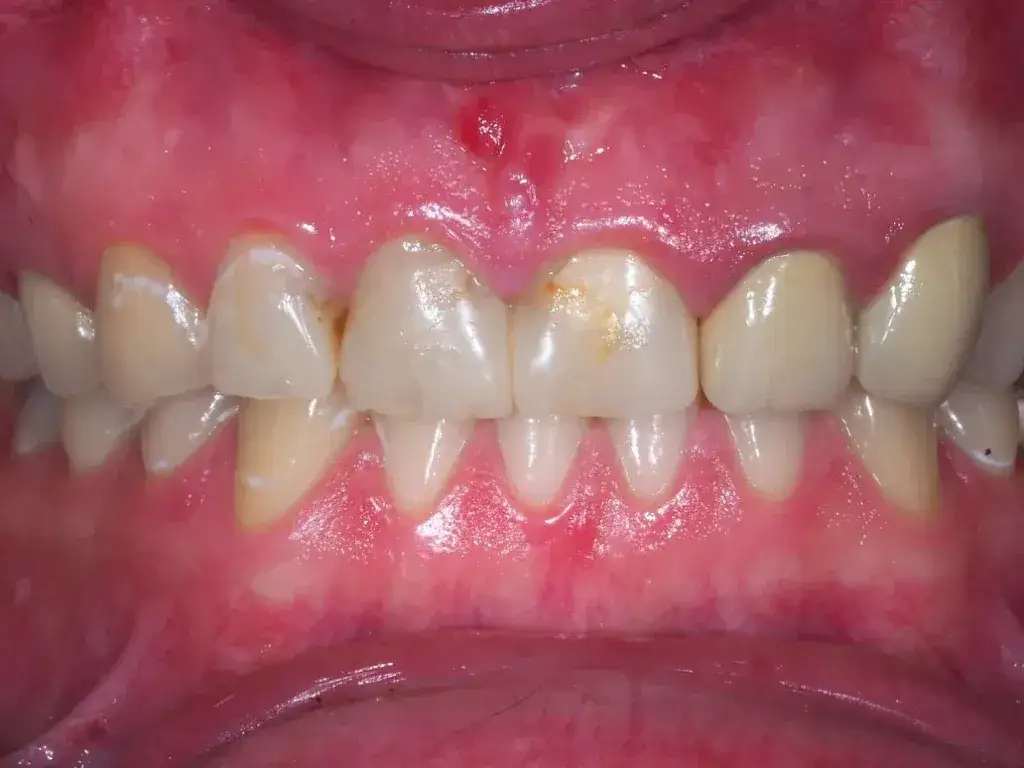

Zapalenie dziąseł u dziecka: Ile trwa i kiedy do dentysty?

Zapalenie dziąseł u dziecka? Dowiedz się, ile trwa (7-14 dni), jakie są objawy i kiedy iść do dentysty. Sprawdź skuteczne domowe leczenie i zapobieganie.